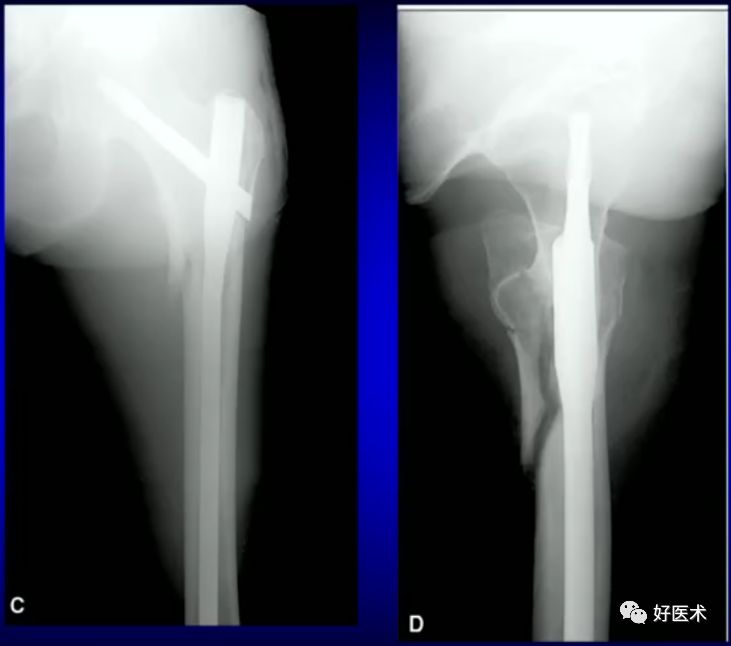

病例:男,34岁,高处坠落伤,仅骨折余正常

术前牵引

开口、定位

术中过程